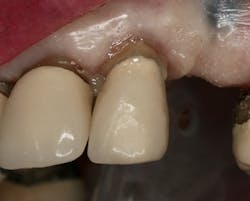

Figure 12: Try-in of PFM crown retrofit after posts were cut to desired length

The excess of the posts was trimmed without water, and the existing crown was then tried in to verify precise fit (figure 12). Once passive fit over the cut post bundle was verified, the intaglio surface of the crown was acid-etched, rinsed, and dried.

FuturabondUadhesive was applied and cured. The intaglio surface of the crown was filled with Rebilda DC cement, which was also used to “buttercoat” the root surface and cut the post bundle. The two segments were then joined and resin-bonded together by using a curing light and waiting the manufacturer-specified time for the dual-cure polymerization reaction to complete (figure 13). The excess cement was removed and the margins checked for any gaps.